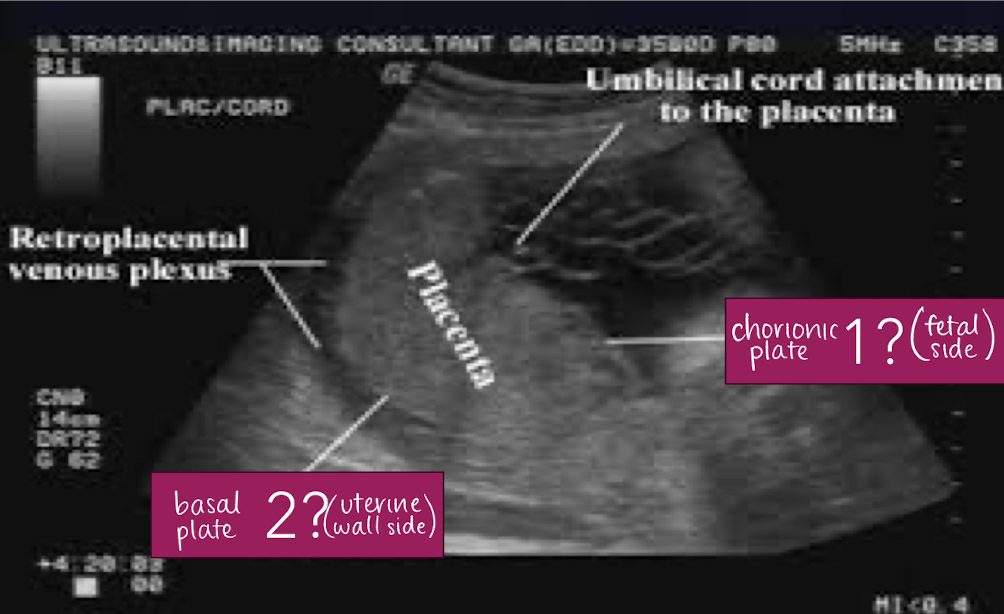

placenta anatomy

divided into 2 parts

chorionic plate (fetal surface)

surface facing amniotic fluid

continuous with chorion

basal plate (maternal surface)

surface facing uterine wall

continuous with decidua basalis

placenta plate facing amniotic fluid/fetus is called…

chorionic plate

placenta plate facing uterine wall/mom is called…

basal plate

SONO: placenta

homogeneous

pebble-gray—mildly more echogenic compared to uterine wall

may be more echogenic in 1st trimester

smooth borders

highly vascular structure

rim of myometrium outside placenta should be noted

prominent maternal vessels may be seen posterior to placenta (anechoic tubes)

placental lakes may also be seen in placenta